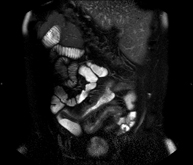

Prova diagnòstica no invasiva que consisteix per obtenir d'imatges d'alta definició anatòmica de l'intestí mitjançant l'ús d'un camp electromagnètic i ones de ràdio (amb un emissor i un receptor). No utilitza radiació ionitzant. Normalment requereix l'ús de contrast paramagnètic (Gadolini). Està indicada principalment en el diagnòstic, el seguiment i el control de la resposta al tractament dels pacients amb Malaltia de Crohn. - RM Rectal